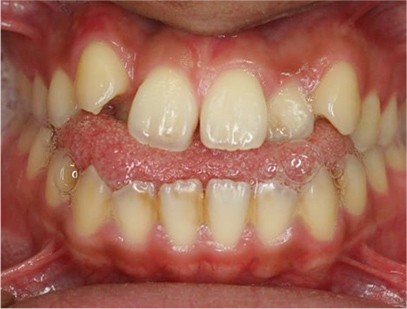

前歯が咬み合ってなく開咬の症例

上下の前歯が咬んでない事と前歯のデコボコを主訴として来院されました。

通常通り検査を行い「前歯部にデコボコを伴う開咬」と診断されました。

舌の悪習癖のために上顎の歯並びの幅が狭いために裏側から拡大し、その後、上顎には裏側に下顎には表側に矯正装置を装着して綺麗に歯を並べてまた咬み合わせも改善しました。

上は裏側に、下は表側にセラミック(白い矯正装置)

治療前後の写真を比べると前歯は綺麗に咬み合っていて、上の奥歯が狭かったのが拡大されており下の奥歯と綺麗に咬み合っていることが解ります。治療期間は患者様の協力が大変に良かったために1年半で終了することができ、現在保定治療を行っております。

• 前歯部の歯並びが綺麗になり、全体的に咬み合わせが治療された事